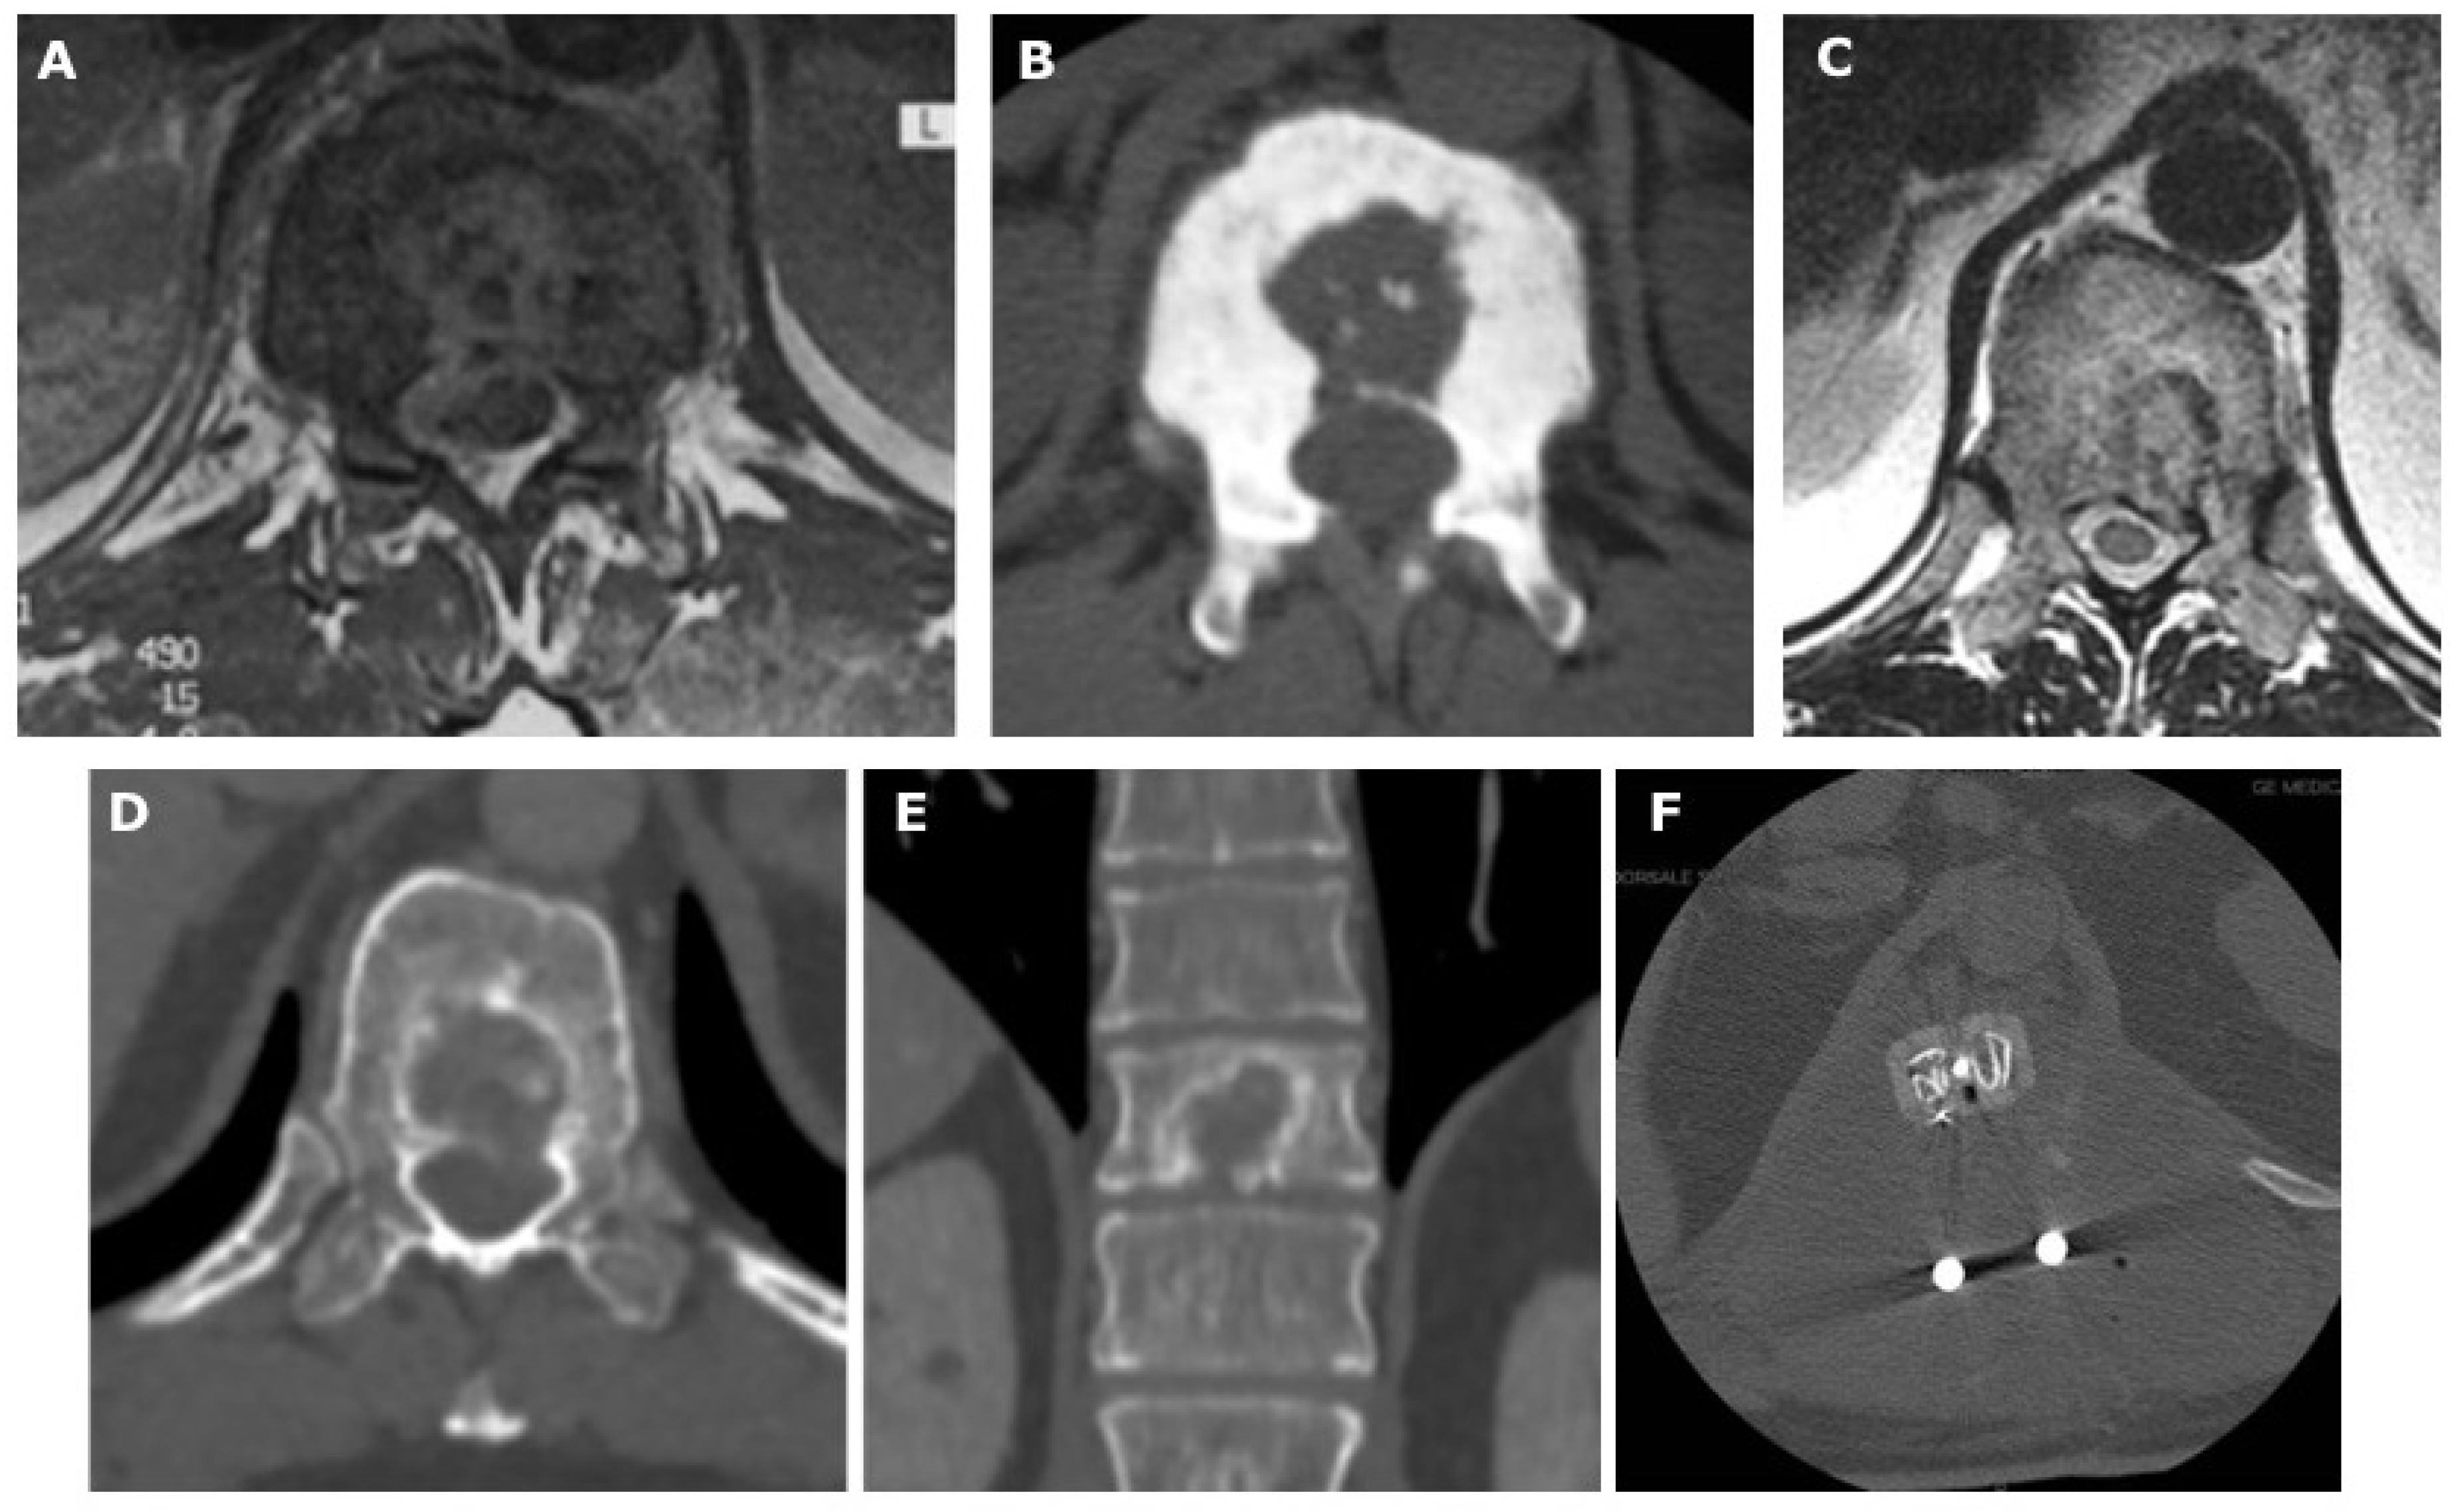

4.2. Differentiating Features on CT

| Spinal Tuberculosis | Cervical and Lumbar spine; A single segment is involved | Collapse and destruction of the vertebra Loss of disc space “Gibbus deformity” Anterior wedging or kyphosis | Erosions, marginal sclerosis, and sequestra formation Lytic lesions Epidural and paraspinal involvement Spinal canal involvement Small bony fragment | relative Blood Flow (rBF) value < 4 relative Blood Volume (rBV) value < 3.5 | Early stage: hypointense on T1-weighted; hyperintense on T2-weighted (marrow edema, inflammation). granulomatous inflammatory response Chronic stage: hypointense on T1-weighted and on T2-weighted images (necrosis, abscess formation) Involvement of adjacent structures (spinal cord, nerve roots, and paraspinal tissues) | Heterogeneous enhancement (necrosis, abscess formation, or granulation tissue) | Early stage: restricted diffusion (low ADC values) Chronic stage: no diffusion restriction with high ADC values | Involvement of vertebral bodies and the related disc with rapid destruction Subligamentous spread with extension into the paraspinal soft tissue with abscesses, usually calcified Extension in epidural space with spinal cord or nerve compression Posterior elements of the vertebra are generally spared |

| Pyogenic Spondylitis | Cervical and Lumbar spine; A single segment is involved | Localized vertebral destruction Loss of disc height Paraspinal soft tissue swelling Bony sequestra, sclerosis, and vertebral collapse | Erosions, sclerosis, and sequestra formation Cortical destruction Sequestration and abscesses | relative Blood Flow (rBF) value < 4 relative Blood Volume (rBV) value < 3.5 | Early stage: hypointense on T1-weighted; hyperintense on T2-weighted (inflammation). granulomatous inflammatory response Chronic stage: hypointense on T1-weighted and on T2-weighted images (necrosis, abscess formation) Involvement of adjacent structures (spinal cord, nerve roots, and paraspinal tissues) | Enhancing inflammatory changes, abscesses, and granulation tissue Ring-enhancing abscesses with peripheral rim enhancement | Early stage: restricted diffusion (low ADC values) Chronic stage: no diffusion restriction with high ADC values | Involvement of vertebral bodies and the related disc with rapid destruction Subligamentous spread with extension into the paraspinal soft tissue with abscesses, usually calcified Extension in epidural space with spinal cord or nerve compression Posterior elements of the vertebra are generally spared |

| Atypical Spinal Tuberculosis | Thoraco-lumbar spine; Multisegmental | Minimal vertebral body involvement Isolated disc space narrowing Abnormal spinal alignment, or signs of instability | Large paravertebral abscesses | Isolated involvement of the posterior elements or a skip lesion pattern Heterogeneous mixed T2-weighted Epidural extension | Involvement of posterior elements Skip lesion separated from each other Extradural spinal cord compression |

| Neoplastic (Primitive) | Mostly Thoracic spine | Vertebral collapse Pathological fractures Abnormal spinal alignment | Destruction, erosion, sclerosis Presence of a bony mass Spinal canal involvement Erosion of the cortical bone Presence of spinal cord compression or nerve root impingement | relative Blood Flow (rBF) value > 4 relative Blood Volume (rBV) value > 3.5 | Location, size, extension Extent of spinal cord compression, evaluate nerve root involvement, and identify the presence of cystic or necrotic components within the tumor Various imaging features on MRI | Intense contrast enhancement in homogeneous or ring-like enhancement | Restricted diffusion (low ADC values) | Vertebral body and posterior elements involvement Preserved disc Halo Sign |

| Neoplastic (Metastasis) | Mostly Thoracic spine | Osteolytic, osteoblastic, or mixed lytic/blastic lesions Destructive bone lesions Loss of vertebral body height Pathologic fractures | Destruction, cortical thinning A soft tissue mass | relative Blood Flow (rBF) value > 4 relative Blood Volume (rBV) value > 3.5 | Location, size, extension Extent of spinal cord compression, evaluate nerve root involvement, and identify the presence of cystic or necrotic components within the tumor Various imaging features on MRI | Homogeneity, heterogeneity, or rim enhancement, can provide insights into the aggressiveness and vascularity of the metastatic lesions | Restricted diffusion (low ADC values) | Vertebral body and posterior elements involvement Preserved disc |